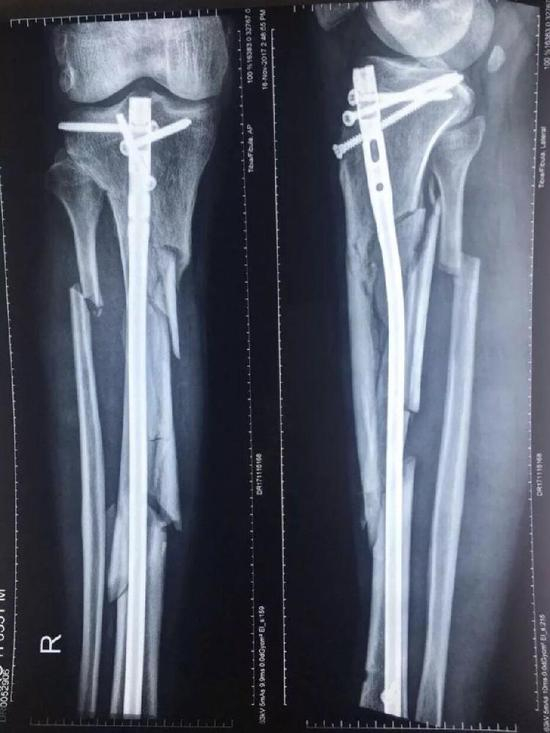

张毅被打的情况发生于2017年10月18日,在廊坊师范学院内,四名歹徒持镐把张毅打伤,致其右腿粉碎性骨折。